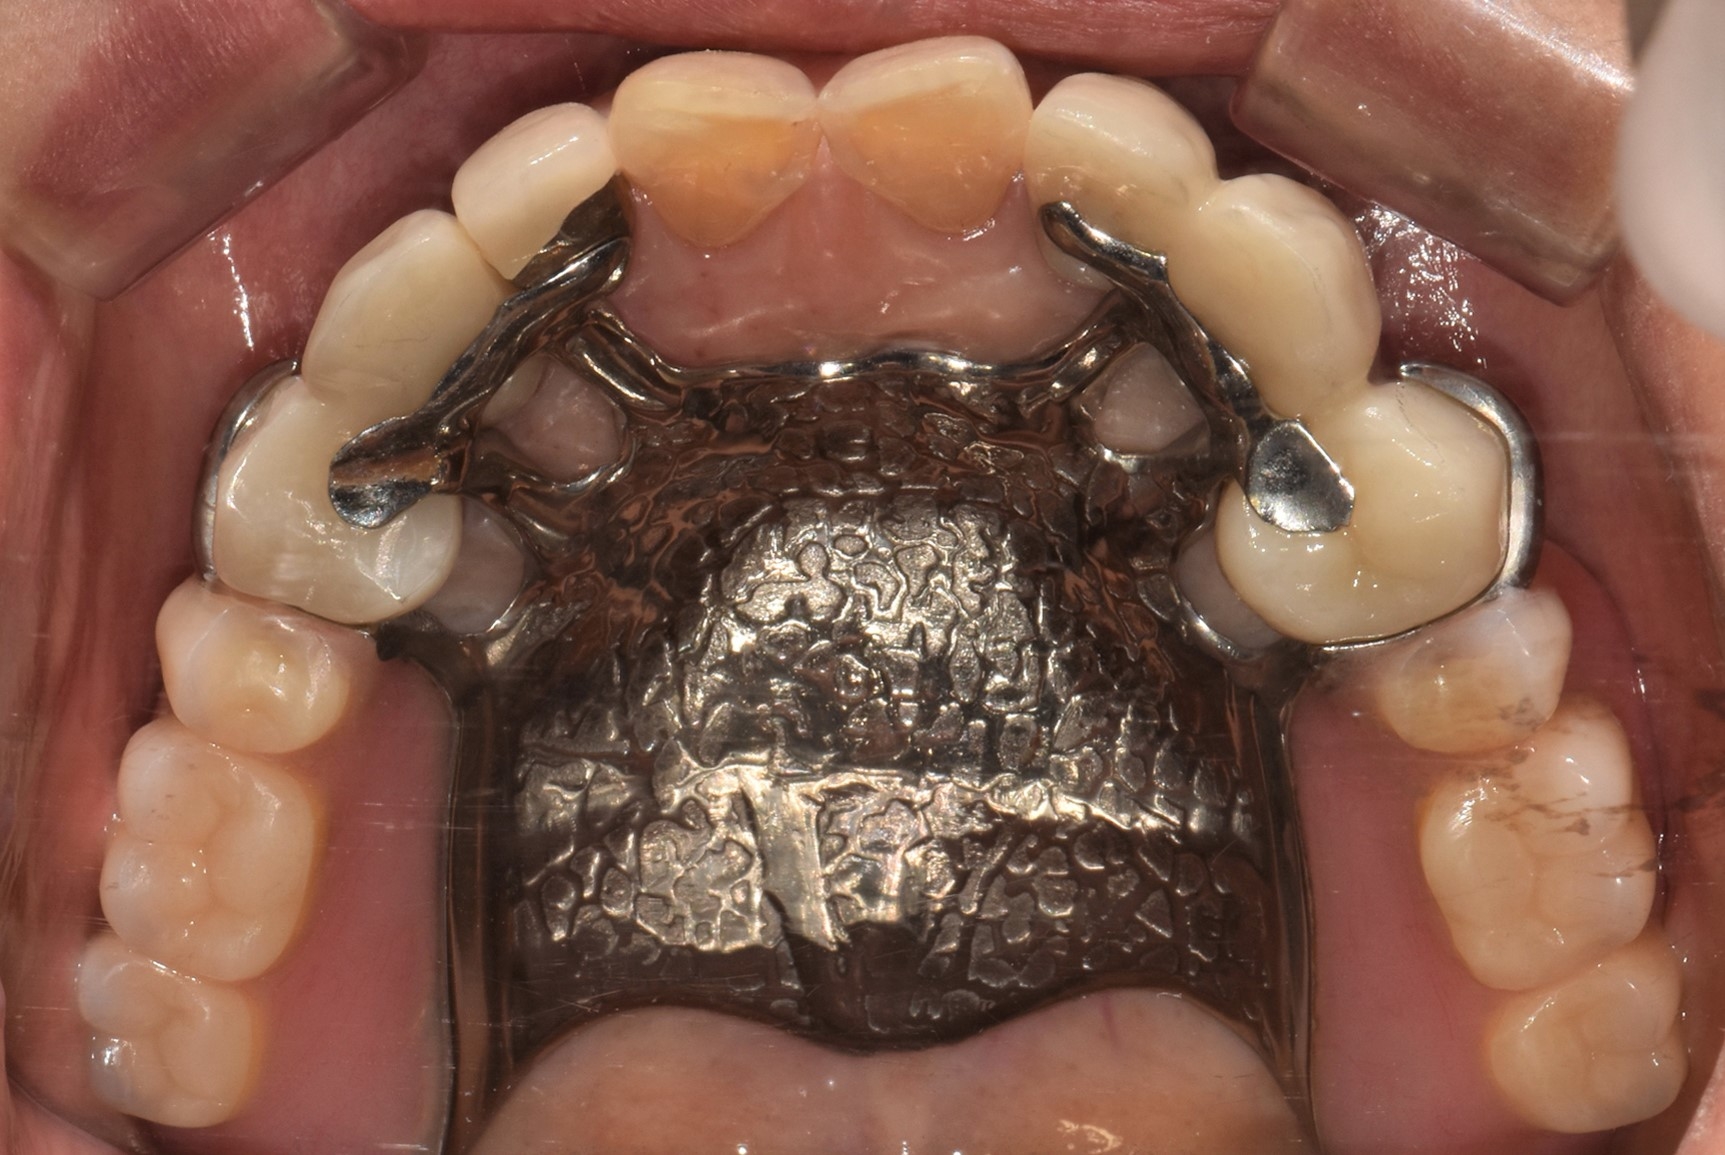

Objectives: Implant-assisted removable partial dentures (IARPDs) have been proposed as a treatment option for partial edentulous patients. However, evidence regarding the merits of implant-assisted removable partial dentures with implant surveyed prostheses is limited. This study was conducted to evaluate the clinical status and complications of IARPDs combined with implant surveyed prostheses in terms of clinical condition, marginal bone resorption, and prosthetic complications.

Methods: Patients treated by IARPDs combined with implant surveyed prostheses and had worn an IARPD at least 12 months were included. 24 patients (25 cases, 12 maxilla and 13 mandible) were selected, and 80 implants used as abutments for IARPDs were surveyed. Average follow-up was 27.6 months and maximum follow-up was 78 months. Implant cumulative survival rate, marginal bone resorption, probing depth, peri-implant inflammation, bleeding, plaque, calculus, and complications were evaluated.

Results: No implant failure was occurred and all implants functioned without clinical mobility. Mean marginal bone resorption of implants at 1 year after loading was 0.772 ± 0.63 mm, and mean probing depth was 3.36 ± 0.06 mm. No patient developed peri-implantitis and no implant failed. Two clasp fractures, one rest fracture, de-cementation, and a porcelain fracture of implant surveyed prostheses were detected at 12 months after loading.